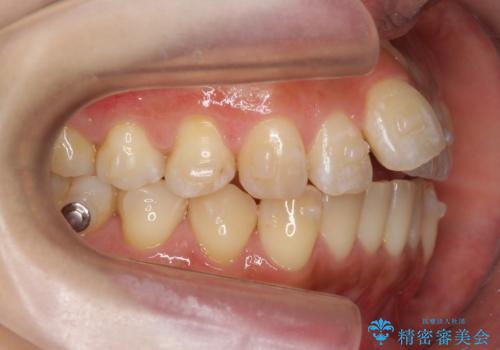

上の奥歯を後ろに下げて治療をしました。

矯正用のミニスクリューを使用しています。

上の前歯もIPR(エナメル質をわずかに削る処置)を行っています。